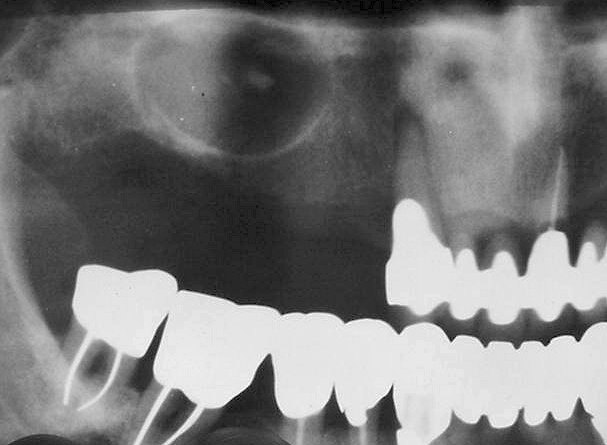

• Ακτινογραφική εικόνα: αρχικά εμφανίζεται σαν διαύγαση με σαφή όρια. Σε προχωρημένα στάδια ακανόνιστες, ποικίλου μεγέθους, ενασβεστιούμενες μάζες μπορεί να εντοπίζονται εντός της οστεολυτικής αλλοίωσης.

• Μπορεί να προκαλέσει μετατόπιση των παρακειμένων δοντιών και απορρόφηση των ριζών τους.

Ενασβεστιουμένη οδοντογενής κύστη (Gorlin)